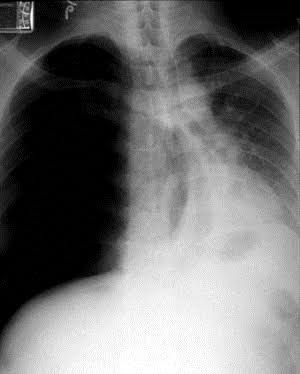

Chest x ray of a patient

Tension pneumothorax

Pneumothorax.....the air filled lung cavity looks jet black